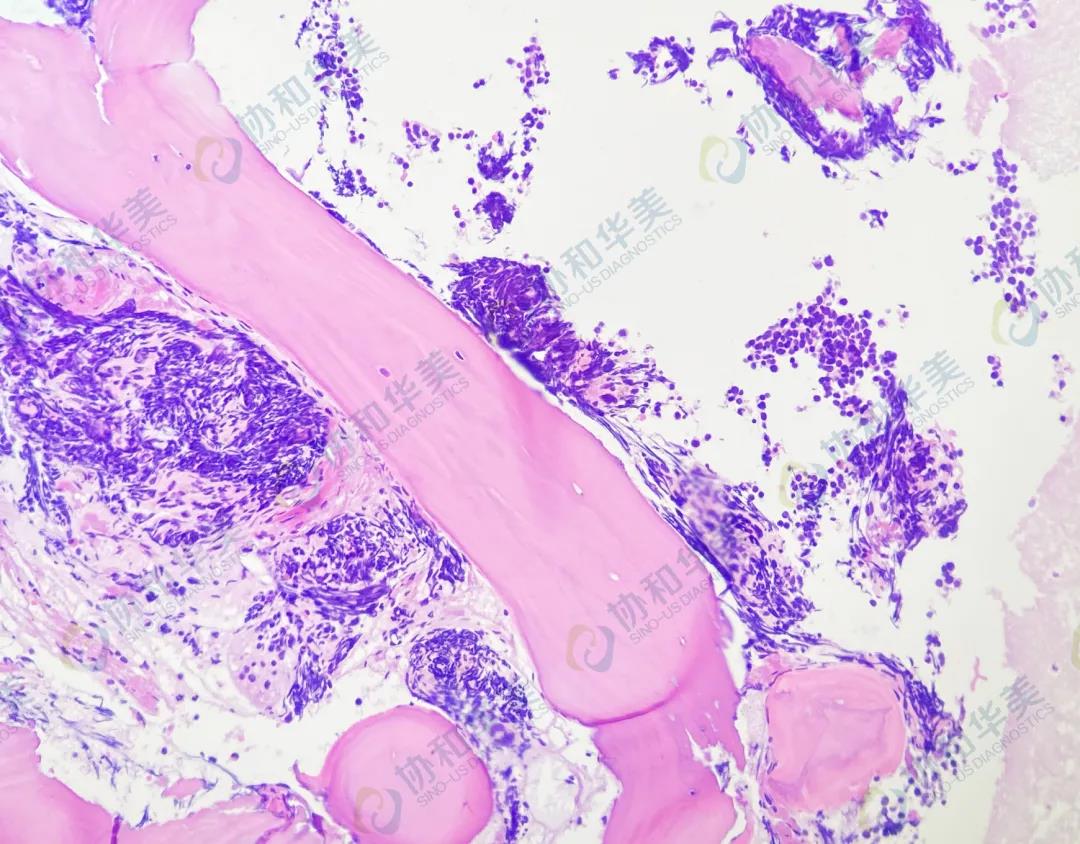

病理

HE染色

转移癌

(结合病史,为小细胞肺癌骨髓转移)